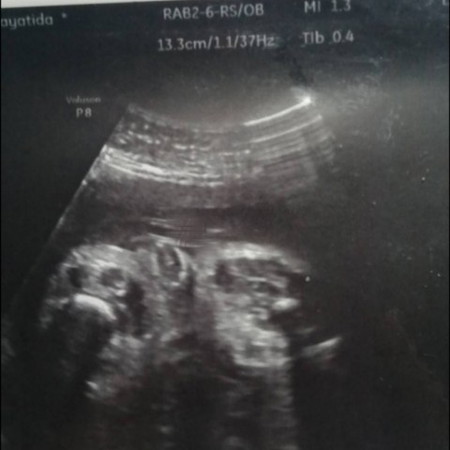

31week2d แล้วจ้า

ดูไม่ออกเลยจ้า เพศ ญ ช ลุ้นหนักมากก? แม่ๆท่านไหนดูเป็นบ้างคะ

รูปนี้มุมไหนคะ แอบ งงๆ ไม่ค่อยชัดเลยค่ะ

เห็นเหมือนจู๋ค่ะ